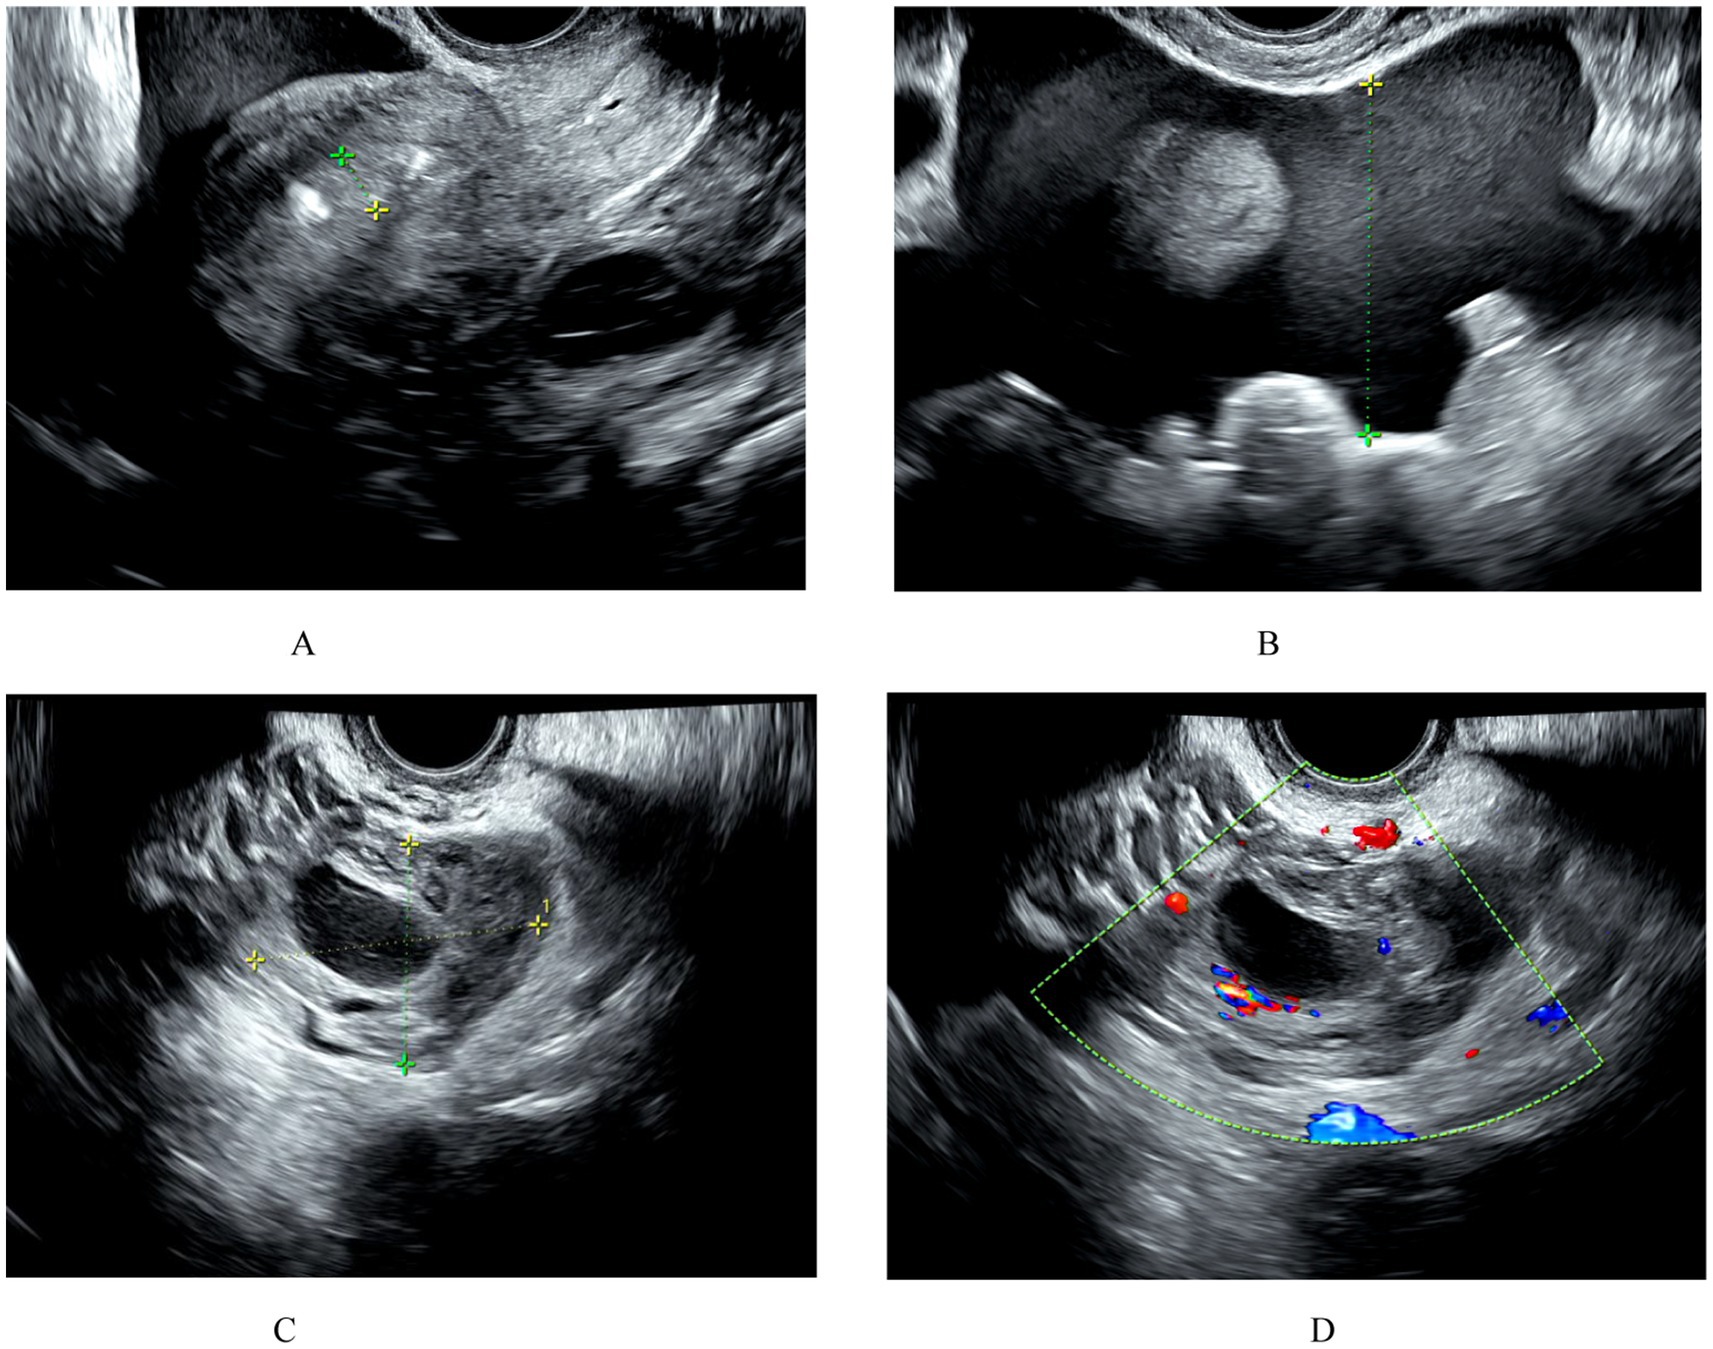

Background: Rectal ectopic pregnancy is classified into primary and secondary types, with primary REP being one of the rarest forms of extrauterine gestation. Currently, there are no standardized guidelines for its diagnosis and treatment. Case presentation: We present a case of primary REP in a 37-year-old woman with acute abdominal pain and massive intra-abdominal hemorrhage. Under the premise of gynecological ultrasound suggesting conventional tubal or ovarian ectopic pregnancy, we employed diagnostic single-port laparoscopy to exclude typical adnexal pregnancies. Through comprehensive exploration of both the upper and lower abdominal cavities, we ultimately confirmed the diagnosis of primary REP. And through coordinated efforts with gastrointestinal surgeons, we performed precise resection of the ectopic gestational tissue while preserving rectal integrity, with prompt control of intra-abdominal hemorrhage. This emergency intervention achieved dual success: lifesaving management coupled with minimally invasive advantages, Enhanced recovery after surgery and resulting in a nearly invisible umbilical incision with optimal cosmetic outcomes. Conclusion :Patients with REP often present with nonspecific early symptoms, leading to frequent misdiagnosis or delayed diagnosis. Definitive diagnosis is typically established only after the onset of severe complications. Through a multidisciplinary approach to this rare case and a systematic review of the literature, we have derived the following important clinical insights: 1.Early diagnosis strategy: early identification of REP requires a multimodal approach, including dynamic monitoring of serum β-hCG levels, pelvic ultrasound, and multimodal imaging assessment with CT/MRI. Diagnostic laparoscopy should be performed when necessary to confirm the location and extent of the lesion. 2. Broadening differential diagnosis considerations: in all women of childbearing age who are considered to be pregnant, especially when intrauterine, tubal, or ovarian pregnancy is not detected by ultrasound, REP should be included in the differential diagnosis. 3. Value of Minimally Invasive Surgery: Single-port laparoscopic surgery has demonstrated comprehensive advantages in such emergency surgeries, including minimal invasiveness, rapid recovery, and cosmetic benefits. However, this technique requires the surgeon to possess advanced skills, and the patient must meet the indications for single-port laparoscopic surgery. This article also provides important reference evidence for the development of standardized diagnostic and treatment protocols for rectal ectopic pregnancy.